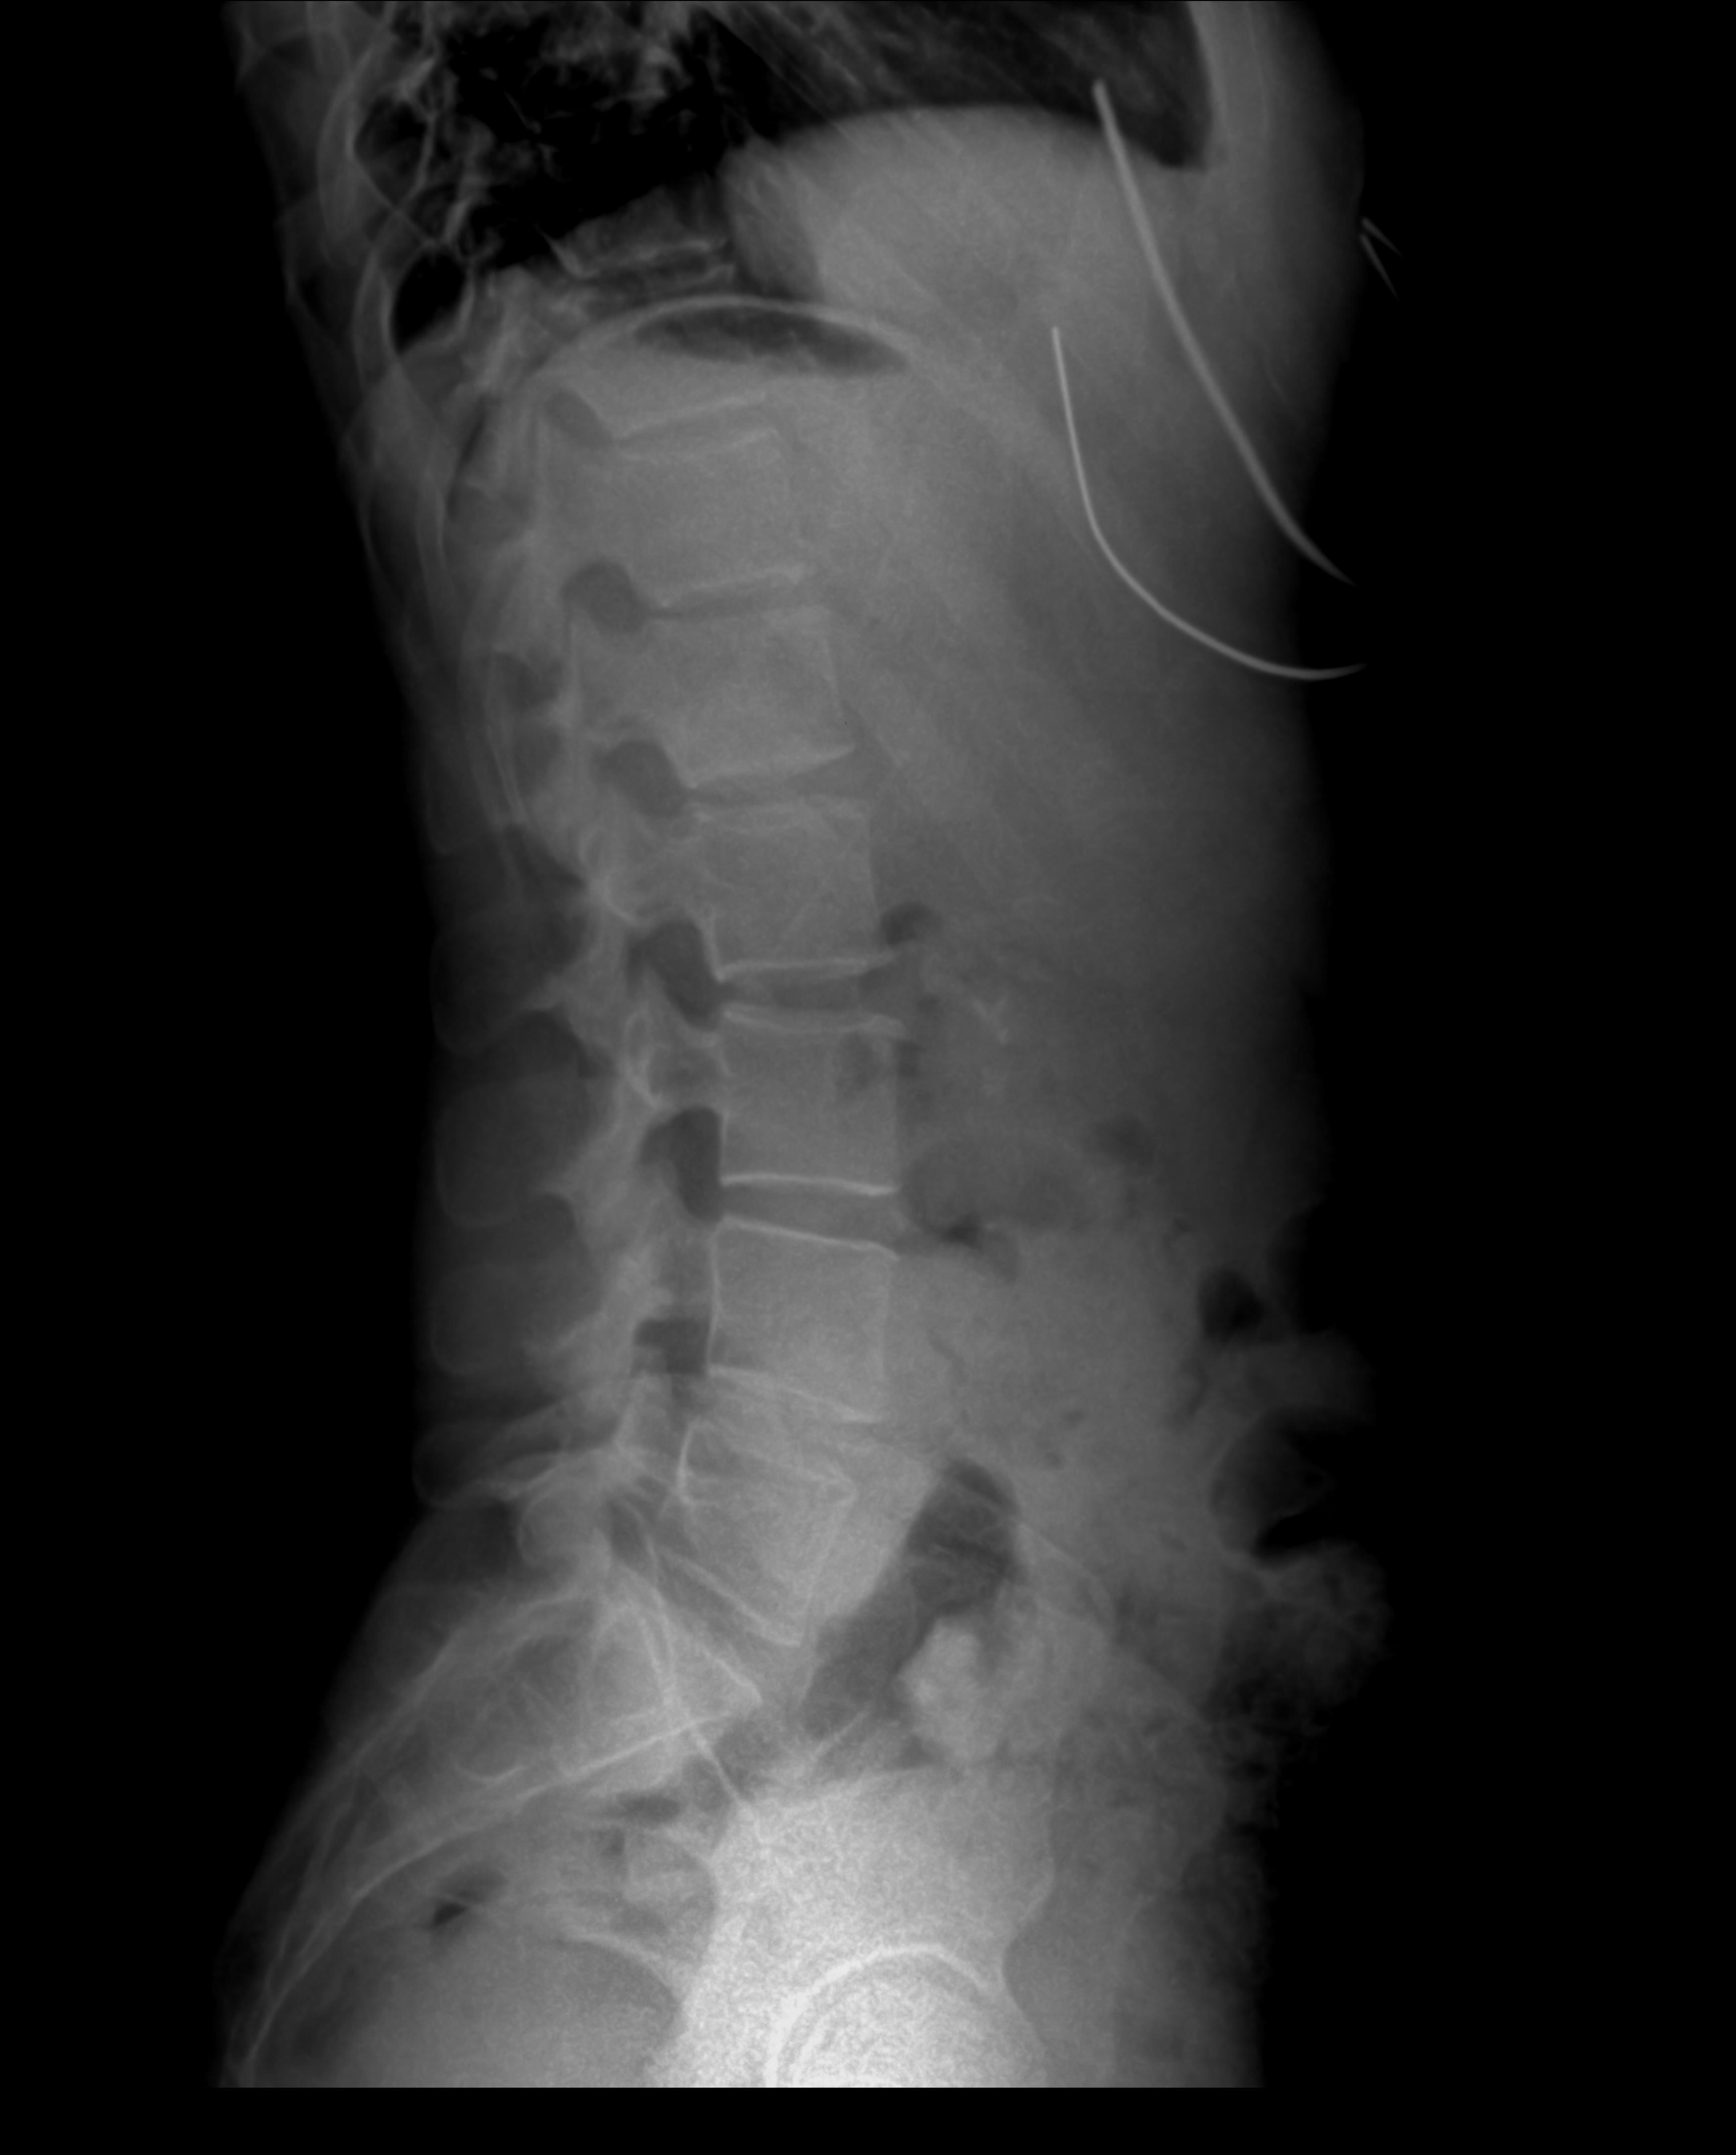

디스크는 척추뼈 사이에서 쿠션 역할을 하는 구조물입니다.

그런데 디스크가 제자리에서 밀려나와 신경을 압박하면

통증이 발생하는데, 이를 추간판 탈출증이라고 합니다.

📌 디스크가 튀어나오면?

허리 디스크: 허리 → 엉덩이 → 다리 → 발까지 통증

목 디스크: 목 → 어깨 → 팔 → 손까지 통증

✅ 틀어진 골반

✅ 잘못된 척추 정렬

✅ 약한 코어 근육

이 세 가지가 무너지면서 디스크가 튀어나오기 좋은 환경이 만들어지는 것입니다.